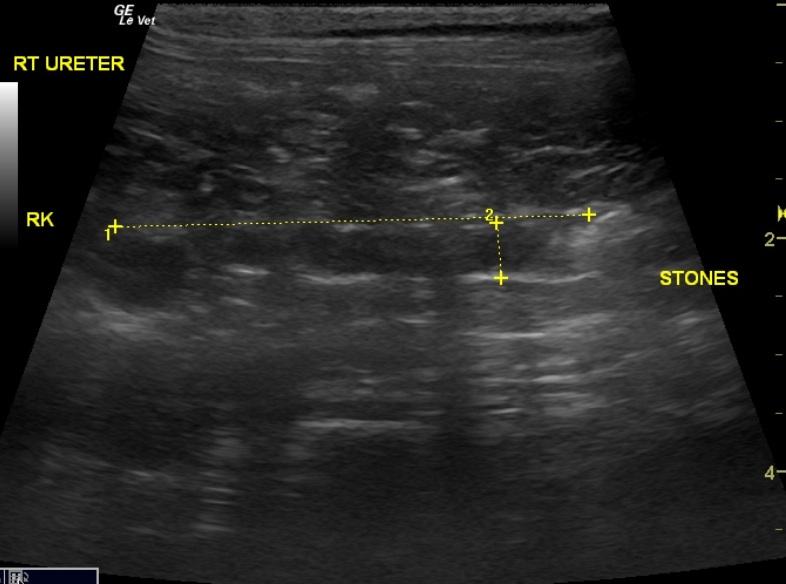

An 8-year-old female spayed DSH cat was presented for weight loss, anorexia, and weakness. The cat was currently on phenobarbital. The only significant abnormality on physical examination was right renomegaly. Urinalysis showed 3+ hematuria, 1+ proteinuria, and elevated microalbuminuria. Azotemia and hyperamylasemia were evident on serum biochemistry.

An 8-year-old female spayed DSH cat was presented for weight loss, anorexia, and weakness. The cat was currently on phenobarbital. The only significant abnormality on physical examination was right renomegaly. Urinalysis showed 3+ hematuria, 1+ proteinuria, and elevated microalbuminuria. Azotemia and hyperamylasemia were evident on serum biochemistry.